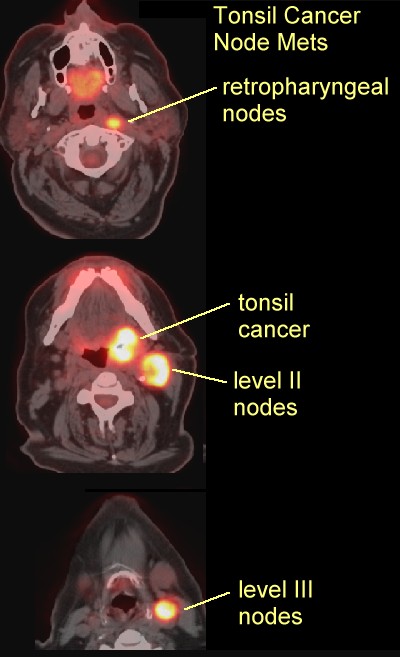

- Tonsil PET

scans:

here,

tonsil nodes,

here ,

here